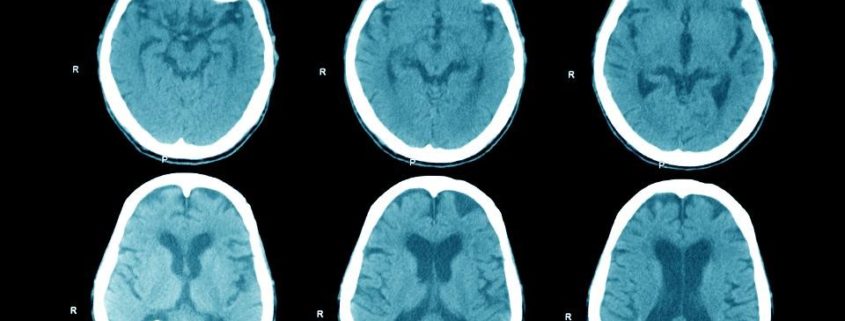

Meer grijze massa = betere prestaties

De onderzoekers veronderstelden dat elk meditatietype volumeverhoging in de corresponderende hersengebieden zou laten zien. Dat is wat ze vonden toen ze na elke module de MRI-scans bekeken en groepen met elkaar vergeleken. Presentie-training liet een grotere dichtheid zien van de grijze stof in de achterste delen van de pre-frontale cortex (aPFC) en de cortex singularis anterior (CCA). Die zijn beiden sterk geassocieerd met gerichte aandacht en zelfregulering. Affect-training resulteerde in grotere dichtheid in hersengebieden die betrokken zijn bij sociale emoties als empathie en compassie. De Perspectief-training bracht veranderingen in hersengebieden die betrokken zijn bij begrip van de mentale staat van anderen. En ook, nog interessanter, in delen die betrokken zijn bij het onderdrukken van het eigen perspectief. Grotere dichtheid van de grijze stof in die gebieden resulteert in betere prestaties op de gelinkte competenties.